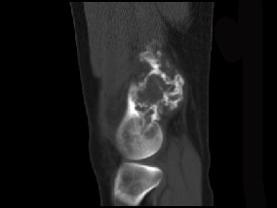

男,34岁,大腿下段疼痛2年,可摸到肿块,请结合所提供图像,选择最佳选项 ( )A、纤维肉瘤B、巨细胞瘤C、软骨肉瘤D、软骨瘤...

问题 男,34岁,大腿下段疼痛2年,可摸到肿块,请结合所提供图像,选择最佳选项 ( )

选项 A、纤维肉瘤 B、巨细胞瘤 C、软骨肉瘤 D、软骨瘤 E、骨肉瘤

答案 C